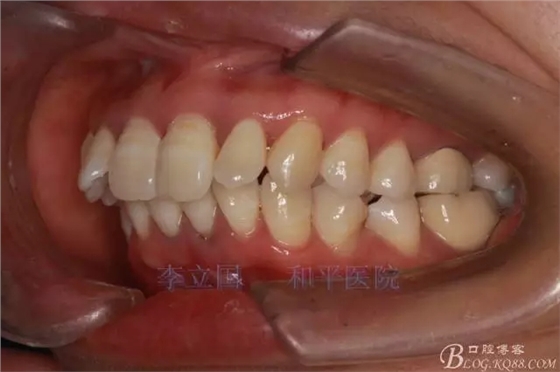

2.Damonclear排齊整平。

3.微種植支抗內(nèi)收上下前牙。

4.調(diào)整咬合關(guān)系。

治療要點(diǎn):

1.患者上前牙直立,面型前突,典型的嘴凸牙不吐,關(guān)鍵是前牙轉(zhuǎn)矩控制,建議使用高轉(zhuǎn)矩托槽。

2.磨牙關(guān)系一側(cè)完全遠(yuǎn)中,一側(cè)遠(yuǎn)中尖対尖,采用兩個(gè)上4,一個(gè)下1的拔牙模式。

3.上頜應(yīng)用支抗釘。表麻下在56牙槽間隔植入,注意因使用的為鈦合金釘,一直保持植入角度與骨面成60度角,不要垂直植入再改變角度。要求即刻加載,即刻加載力值2盎司。

4.使用長(zhǎng)牽引鉤,使?fàn)恳咏项M骨阻抗中心,防止上頜骨的順時(shí)針旋轉(zhuǎn)。

5.回收過程中,上下前牙輕搖椅,防止覆合加深。